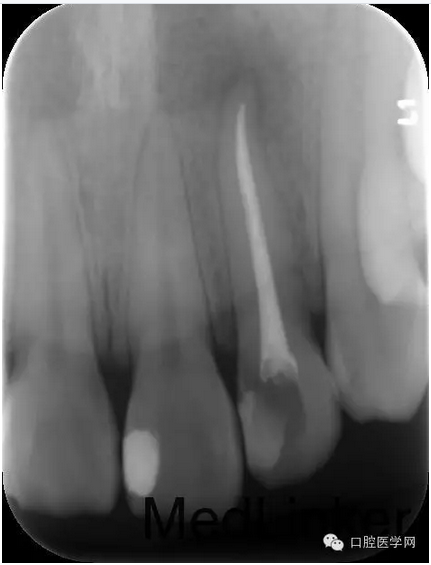

第四次:復(fù)診無(wú)不適。叩診無(wú)不適,無(wú)松動(dòng)。復(fù)查X線片,根尖密度減低區(qū)明顯減小,玻璃離子體部分去除,樹(shù)脂充填,調(diào)牙合,拋光。醫(yī)囑待18周歲后行冠永久修復(fù)。